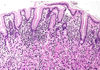

Describe this pathology

GERD

acid-pepsin injury increases cell death and desquamation at surface, w/ compensatory basal hyperplasia (+ elongated submucosal rete pegs)